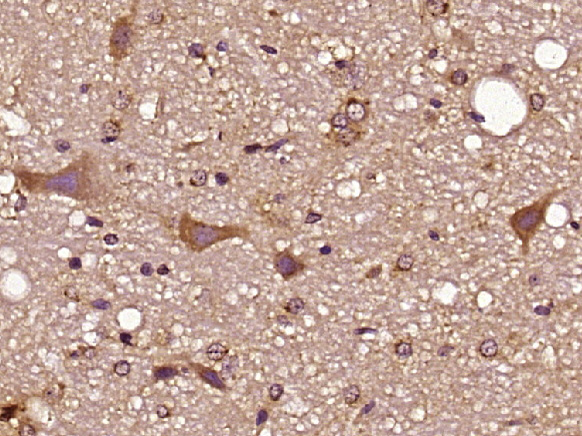

Paraformaldehyde-fixed, paraffin embedded (Rat brain); Antigen retrieval by boiling in sodium citrate buffer (pH6.0) for 15min; Block endogenous peroxidase by 3% hydrogen peroxide for 20 minutes; Blocking buffer (normal goat serum) at 37°C for 30min; Antibody incubation with (Synaptogyrin 2) Polyclonal Antibody, Unconjugated (bs-11374R) at 1:400 overnight at 4°C, followed by operating according to SP Kit(Rabbit) (sp-0023) instructionsand DAB staining.